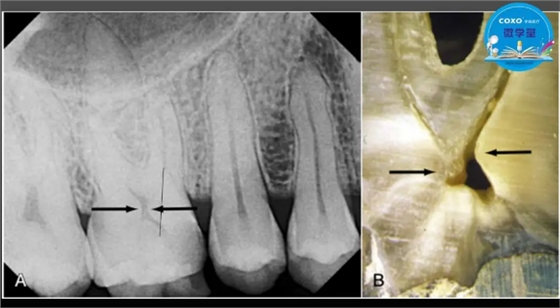

主任医师,牙体牙髓副主任, 广东省口腔医院牙体牙髓科 主任医师。2003年硕士研究生毕业,研究方向为牙体牙髓病学,擅长于牙体牙髓病的诊断、龋齿、牙髓炎、根尖周病的治疗以及前牙美容修复。